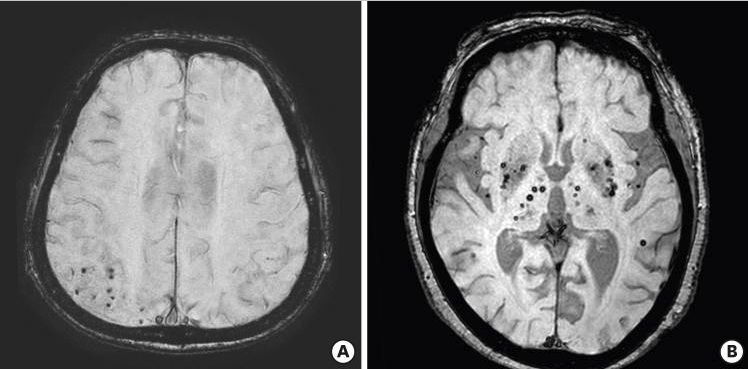

자세한 내용은 아래 논문을 참고해주세요! 출처 : https://www.ncbi.nlm.nih.gov/pmc/articles/PMC6428007/